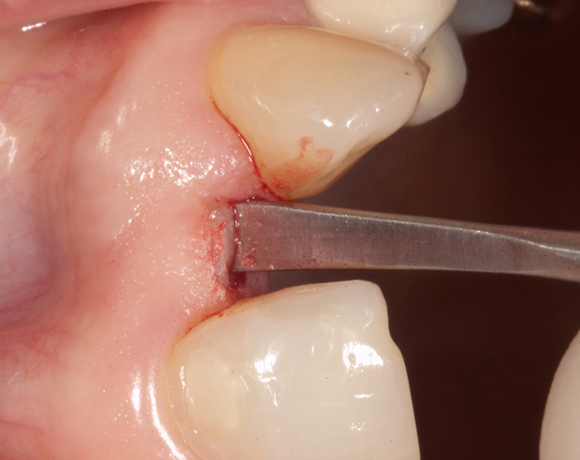

Im vorliegenden Patientenfall musste der Zahn 22 nach erfolgloser Endodontie entfernt werden. Die Nachbarzähne waren kariesfrei, es wurde eine Marylandbrücke (eine Brücke mit zwei Flügelchen, die palatinal an den Nachbarzähnen verklebt werden) oder ein Implantat besprochen. Die Patientin hat sich für ein Vollkeramikimplantat entschieden. In der Diashow wird der operative Eingriff bis zur fertigen Krone gezeigt. Die Einheilzeit betrug drei Monate.